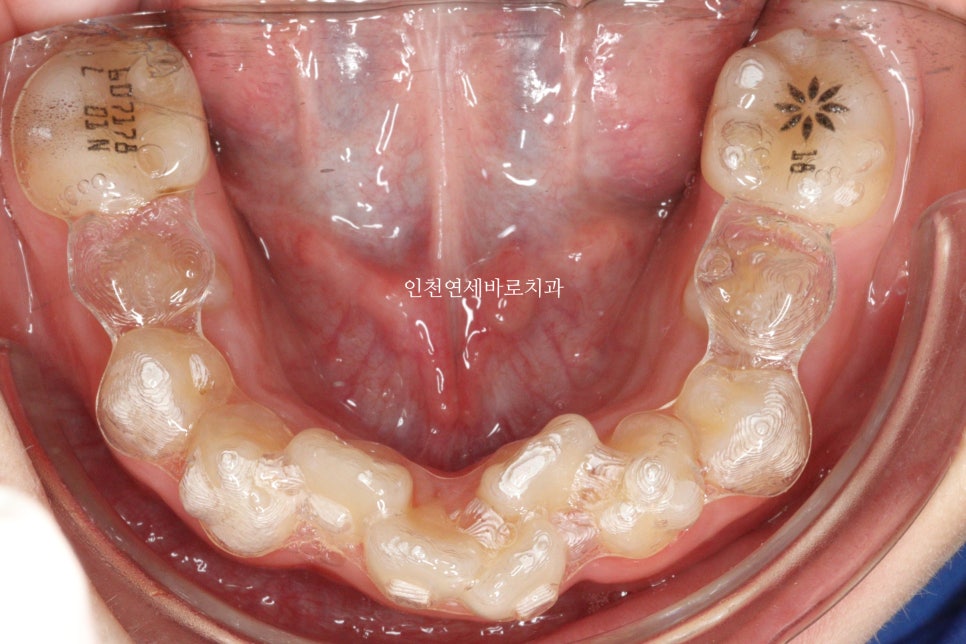

그리고 올해 12월 초에 병원에 왔을 때의 모습입니다.

100점은 아니지만, 이제는 거의 모든 치아가 배열된 것 처럼 보입니다.

아직 이 친구는 3개월의 치료 유효기간이 남아있고, 2024년 2월정도에 마지막 재제작을 준비하고 있습니다.

굳이 안해도 될지 모르지만, 100점을 위해 보호자분과 이야기해서 2월에 재제작을 정한 상태입니다.